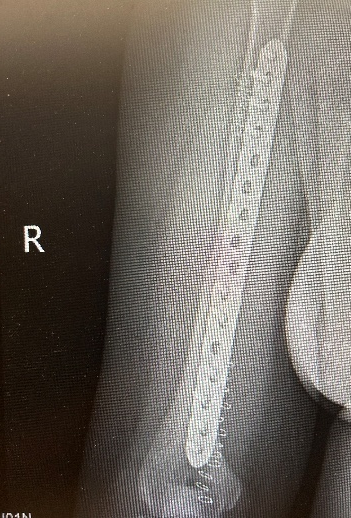

10月1日,李女士(化名)因车祸致右上肢骨折,13:30入院,黄磊医师团队完善各项检查后于18:00实行右肱骨骨折切开复位内固定术, 20:00安返病房。

图片